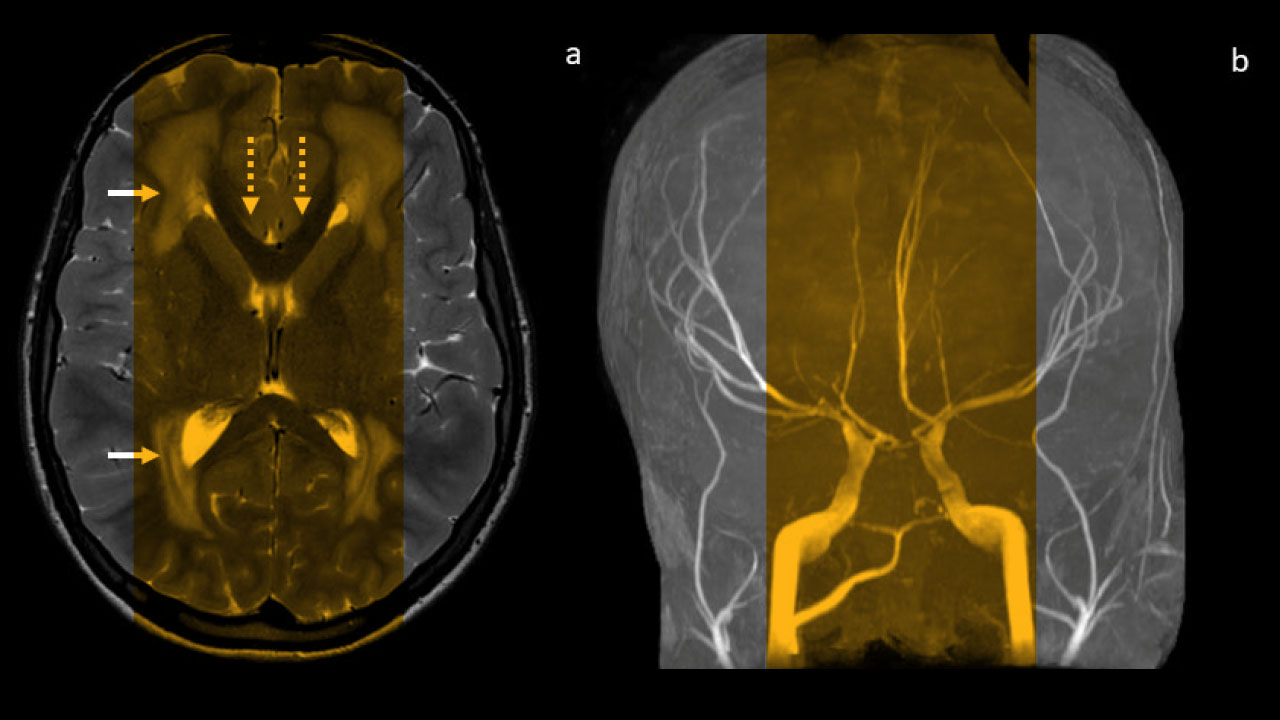

The primary concern when it comes to administering anesthesia to kids with MSMDS is that anesthesia can cause changes in blood pressure. When a healthy child undergoes anesthesia, their body compensates for drops in blood pressure by signaling smooth muscle to squeeze. But because MSMDS weakens the smooth muscle in blood vessels, these patients are prone to dangerous blood pressure drops that reduce blood flow to their organs. What’s more, MSMDS often causes abnormalities of the blood vessels around the heart and to the brain, increasing patients’ risk of stroke or aneurysm while under anesthesia.